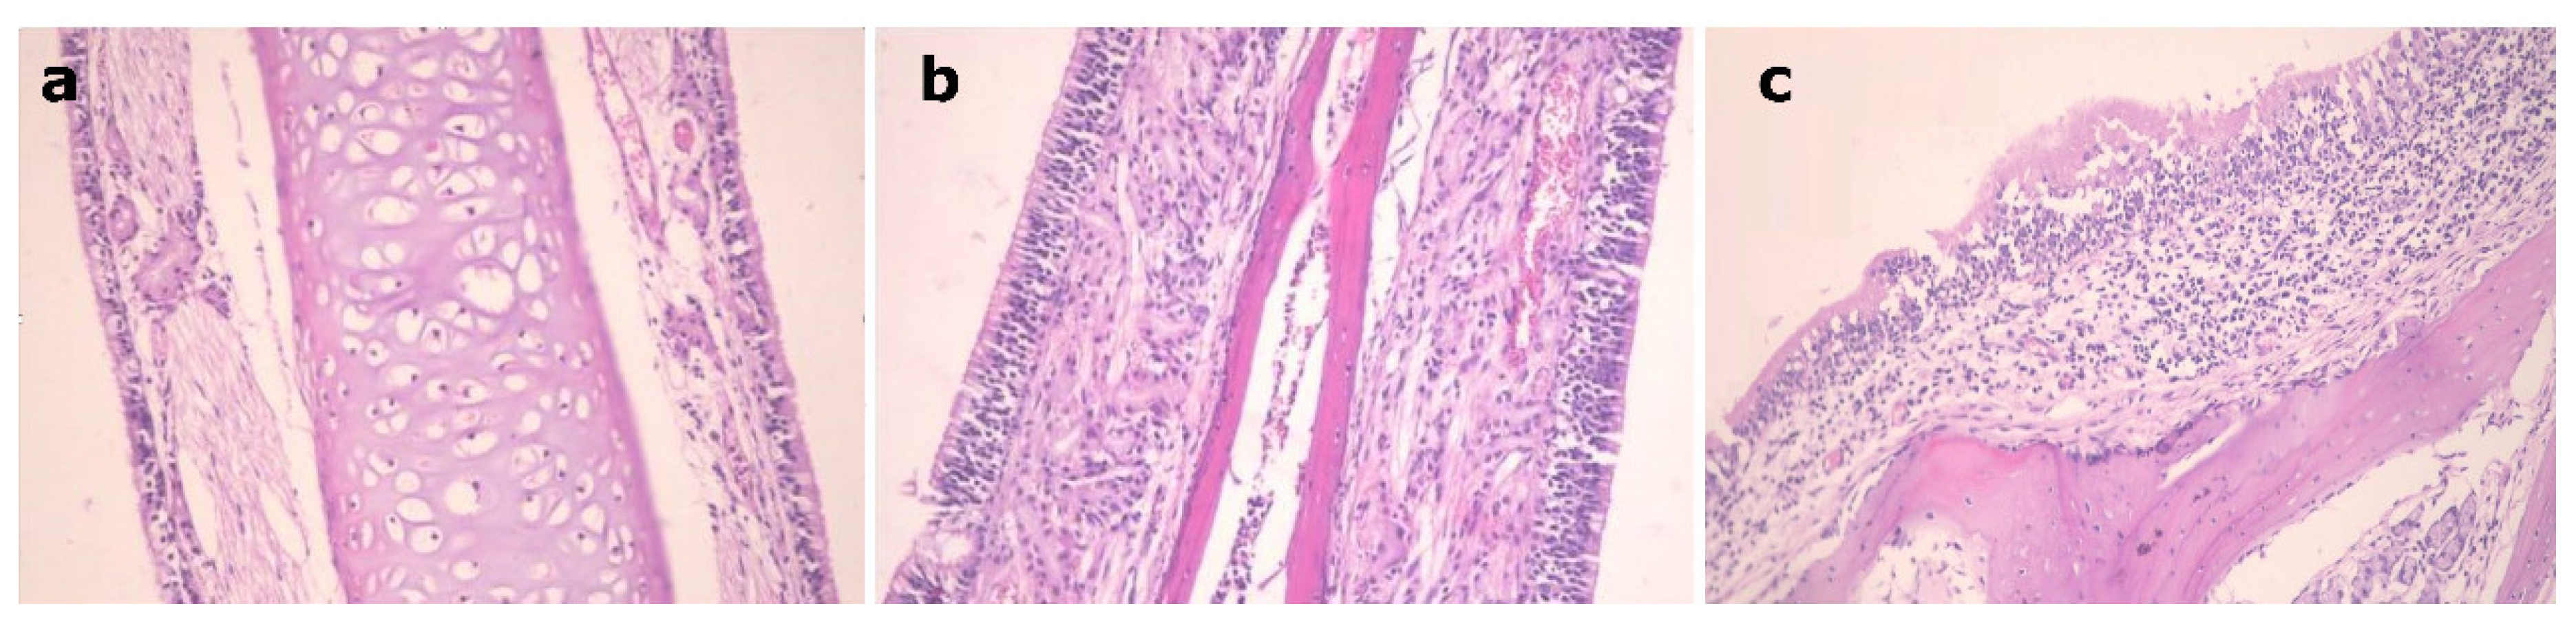

3.7. Histopathological Study

Figure 6 shows the nasal mucosal tissue of the control group, Figure 6a, the group that received a nasal solution of the drug, Figure 6b, and the group that received the EH mucoadhesive emulsomes, Figure 6c. Group (c) showed normal tissue features with preservation of the ciliated respiratory epithelium without obvious hyperplasia or necrosis of nasal mucosa in a similar way just as that of the other two groups. This indicates that the EH mucoadhesive emulsomal formulation with its components has no ciliotoxic effect on the nasal mucosa and can be applied safely.

Figure 6.

Nasal mucosal tissue of: (a): control mouse, (b): mouse received EH solution, (c): mouse received EH mucoadhesive emulsomes.